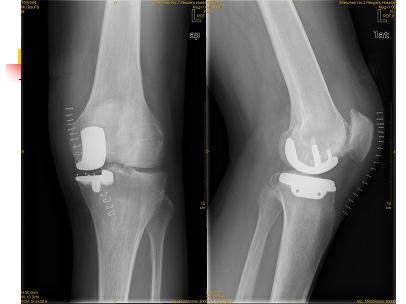

膝关节单髁置换

男性,25岁,行走疼痛2年。

术中见单髁破坏严重,病理为:剥脱性骨软骨炎